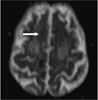

MRI scans of the head revealed acute infarcts (arrows) in the right corona radiata, right centrum semiovale, and anterior and posterior corpus callosum.

In this patient, the syndrome manifested by her left hand can be attributed to the posterior callosal infarct, while the grasping nature of her dominant right “alien” hand may result from a new anterior callosal infarct combined with the prior parietal lobe infarct. Despite the association of this syndrome with Alzheimer- type dementia, we believe our patient's condition was related to the new infarcts.